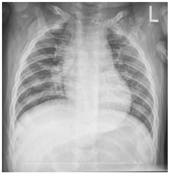

病例1 患儿,男,6个月5 d(纠正胎龄4个月),因"咳嗽2周,加重伴发绀6 d"于2019年4月25日入院。入院2周前开始出现零星咳嗽,6 d前咳嗽加重,呈痉挛性鸡鸣样咳,剧咳时面色潮红,偶有口周发绀,曾外院住院6 d(予阿奇霉素抗感染、雾化、祛痰止咳等治疗),咳嗽无好转,遂来我院。患儿系第1胎第1产,因胎膜早破于29+2周早产,出生体重1.55 kg,出生至今未接种百白破疫苗。患儿父母、奶奶同期均有咳嗽(与患儿有密切接触)。查体:T 36.8 ℃,P 126次/min,R 32次/min,体重8.0 kg。精神尚可,前囟平软,无鼻煽及点头呼吸,三凹征阴性,肺部呼吸音粗,闻及少许湿啰音;心腹查体无阳性体征。入院3 d前在外院辅助检查:血常规:WBC 22.78×109/L,N 22.3%,L 60.1%,Hb 133 g/L,PLT 513×109/L;CRP 6.78 mg/L;X线胸片(图1)提示:双肺多发性病变,并右肺上叶节段性含气不全;查百日咳DNA定性(+)。入院诊断:百日咳肺炎。辅助检查:入院当天血常规:WBC 33.8×109/L,L 92.1%,Hb 130 g/L,PLT 577×109/L;CRP 0.3 mg/L;肝肾心功能基本正常;痰培养及血培养阴性。入院第5天血常规:WBC 22.8×109/L,L 76.2%,Hb 131 g/L,PLT 547×109/L。入院第16天血常规:WBC 14.1×109/L,L 67.0%, Hb 130 g/L,PLT 404×109/L;CRP 1.6 mg/L。入院第24天血常规:WBC 13.4×109/L,L 46%, Hb 124 g/L,PLT 661×109/L;CRP 0.32 mg/L。治疗:入院后予阿奇霉素[10 mg/(kg·次)×3 d]抗感染、布地奈德联合异丙托溴铵雾化每8小时1次、肺力咳合剂止咳治疗,患儿入院第1天痉挛性咳嗽仍明显,20~30阵/d,剧咳时20余声/阵,伴口周发绀1~2次/d,无发热。入院第2天,经家长签字同意后,予加用大剂量盐酸氨溴索注射液10 mg/(kg·次) 每天2次(上海勃林格殷格翰药业有限公司,注册证号H2150468,国药准字20140032,规格2 ml:15 mg),并加入5%葡萄糖水50 ml静脉滴注。大剂量盐酸氨溴索治疗第3天患儿痉挛性咳嗽较前缓解(24 h痉挛性咳嗽10~20阵,每阵5~10声,无再发绀及呕吐);治疗第7天痉挛性咳嗽明显缓解(24 h痉挛性咳嗽5~10阵,每阵5~10声,无伴发绀及呕吐);治疗第10天予口服常规剂量氨溴索片(15 mg/次,每天3次)带药出院。患儿出院第2天咳嗽再次加重(24 h痉挛性咳嗽20余阵,每阵10~20声不止,无伴发绀及呕吐),出院第3天再次住院治疗,并再次予大剂量盐酸氨溴索[10 mg/(kg·次),每天2次×13 d]祛痰、布地奈德联合异丙托溴铵雾化每6小时1次治疗。再次住院第4天患儿痉挛性咳嗽缓解(24 h痉挛性咳嗽10~20阵,每阵8~15声,无再发绀及呕吐),再次住院第7天咳嗽明显改善(24 h痉挛性咳嗽5~10阵,每阵5~10声,无伴发绀及呕吐),治疗第13天零星咳嗽,无呈痉挛性咳嗽,好转出院,两次住院期间无全身皮疹、腹泻、休克等过敏表现,出院诊断:百日咳肺炎。出院后2周后电话随访:患儿偶有间断单声咳嗽,5~6次/d,3~5声/阵,期间无阵发性痉挛性咳嗽及呼吸困难,一般情况可。